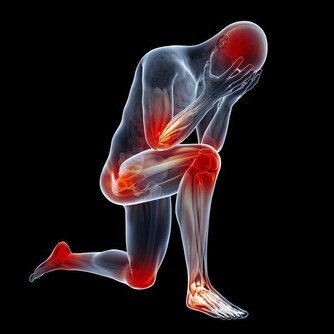

人身體上的器官都是有一定的使用壽命的,保養不當就會減少它的使用壽命,

人體膝關節的使用壽命一般有60年,而且膝關節的損耗是無法修復的,如何延長膝關節的使用壽命呢?

關節的壽命是有限的。一旦關節“氣數已盡”,就會引發各種關節病!關節的壽命主要是由基因決定的,一般的健康壽命是60年。

想必大家都聽過“樹老根先枯,人老腿先衰”,現在不僅僅是老年人經常出現膝蓋酸痛,很多的年輕人也會時不時出現膝蓋疼痛,這是因為什麼呢?

不論是跑跳蹲跪,很多生活習慣都會不經意間對膝關節造成影響。

而且膝蓋問題也逐漸在年輕化。解決這個問題並不難,只需要改變大家的運動習慣即可。

膝蓋不是身體中最常受傷的部位,卻是最薄弱、要求最高的關節,原因是它們經常承受的人的整個重量,而且由於活動範圍大,其結構使它們比髖關節和踝關節更在衝擊下更脆弱。